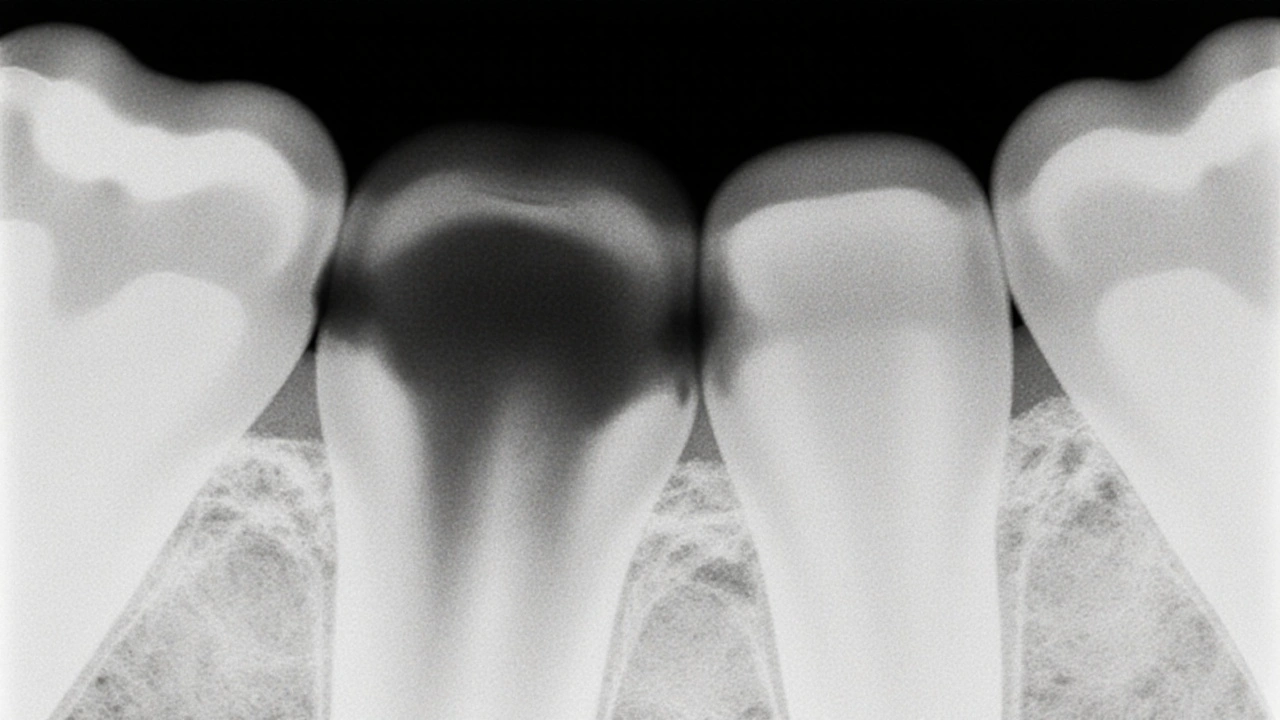

• Oklužní kaz: Vyskytuje se na čelistních plochách zubů, kde se jídlo zadržuje. Na rentgenu vypadá jako malá tmavá škvrna mezi zuby, často v místě, kde se zuby dotýkají. Je těžký na zjištění zvenčí, protože je skrytý mezi zuby. Rentgen je jediný způsob, jak ho včas odhalit.

• Proximální kaz: Podobný oklužnímu, ale nachází se na stranách zubů, kde se dotýkají sousedních zubů. Na snímku vypadá jako široká tmavá páska, která se táhne od povrchu zubu směrem k jádru. Často se přehlíží, protože není vidět při prohlídce.

Rekurentní kaz pod plombou s viditelnou ztrátou kosti kolem kořene.